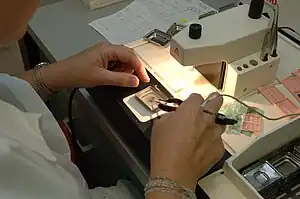

The field of histology that includes the preparation of tissues for microscopic examination is known as histotechnology. Job titles for the trained personnel who prepare histological specimens for examination are numerous and include histotechnicians, histotechnologists,[11] histology technicians and technologists, medical laboratory technicians, and biomedical scientists.

Sectioning

For light microscopy, a knife mounted in a microtome is used to cut tissue sections (typically between 5-15 micrometers thick) which are mounted on a glass microscope slide.[9] For transmission electron microscopy (TEM), a diamond or glass knife mounted in an ultramicrotome is used to cut between 50 and 150 nanometer thick tissue sections.[9]

A limited number of manufacturers are recognized for their production of microtomes, including vibrating microtomes commonly referred to as vibratomes, primarily for research and clinical studies. Precisionary Instruments is a known producer of microtomes and vibratomes for research and clinical studies. Additionally, Leica Biosystems is known for its production of products related to light microscopy in the context of research and clinical studies.[18][19]